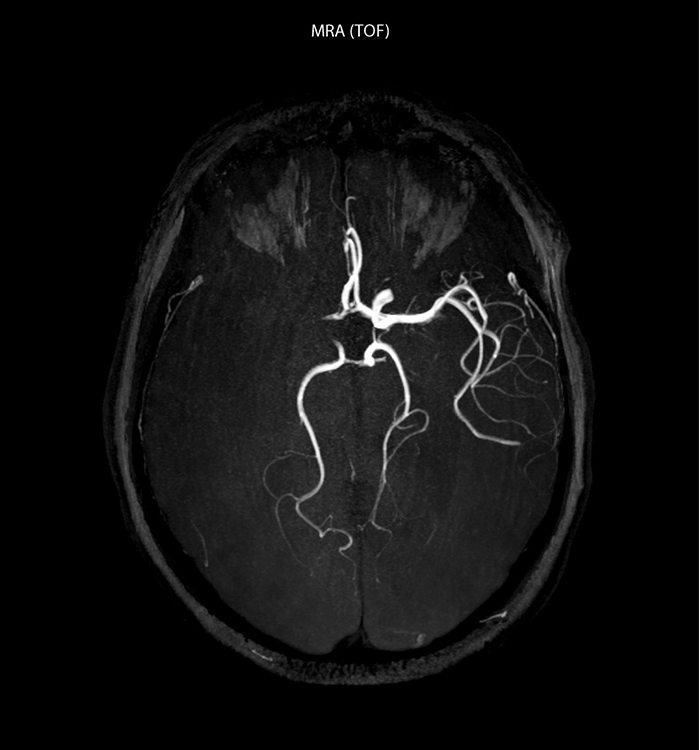

“Every center is different, but for me the ideal protocol for stroke includes diffusion weighted imaging, FLAIR, and fast susceptibility imaging,” says Dr. Savatovsky. “Our fast susceptibility weighted imaging takes 50 seconds, so it’s as fast as T2*-weighted imaging. It visualizes hemorrhage but also the clots. We also do 3D MR angiography that provides information on cervical and brain vessels. If the patient does not need immediate treatment, or if additional information is needed to decide on treatment, we might also add perfusion imaging and post-contrast T1-weighted imaging.”

The hospital uses the 32-channel dS Head coil for every examination type that doesn’t include the lower neck. “This coil’s biggest advantage is the exceptional SNR. This allows us to use higher acceleration factors than with the standard coil.” “In some cases, the high resolution that this coil provides is really necessary. For example, in a head and neck case when we look for a small lesion or small vascular conflict, or in IAC imaging or fifth cranial nerve imaging, we want to achieve very good spatial resolution. In brain disease it’s always better to get more details than less. We gain more diagnostic confidence when we have more information.”